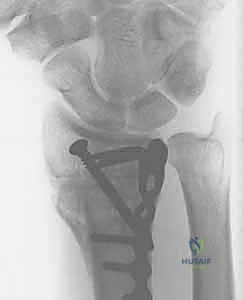

5. التثبيت بصفائح التيتانيوم (Internal Fixation)

للحفاظ على الوضع الجديد والمثالي للعظم، يتم استخدام صفائح تيتانيوم متقدمة ذاتية الغلق (Volar Locking Plates). هذه الصفائح مصممة تشريحياً لتلائم شكل الكعبرة، وتوفر تثبيتاً قوياً جداً يسمح للمريض ببدء تحريك أصابعه في اليوم التالي للعملية.

4. الترقيع العظمي (Bone Grafting)

عندما يتم تعديل زاوية العظم وفتحه، يتكون فراغ عظمي. لضمان التئام سريع وقوي، يقوم الدكتور هطيف بملء هذا الفراغ بطعم عظمي (Bone Graft). يمكن أخذ هذا الطعم من عظم الحوض الخاص بالمريض، أو استخدام بدائل العظم الصناعية عالية الجودة.